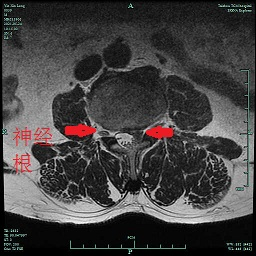

前段時間,臺州市中醫(yī)院就來了一名“腰椎間盤突出癥”患者。59歲的尹先生自訴有“腰椎間盤突出癥”病史10余年,住院前3天突然出現(xiàn)明顯的左側(cè)腰腿痛,久坐或走路時疼痛劇烈,難以忍受,“感覺自己左側(cè)大腿內(nèi)側(cè)的肉都是死的,一點感覺都沒有,會不會癱瘓了?”這可把尹先生嚇得不輕,以為自己是中風(fēng)了,馬上入住了醫(yī)院神經(jīng)內(nèi)科,后來做了腰椎磁共振,MR提示:腰3∕4椎間盤向上脫垂,壓迫相應(yīng)節(jié)段左側(cè)神經(jīng)根。經(jīng)骨科顏峰主任會診后,轉(zhuǎn)入骨科擬行“椎間孔鏡下髓核摘除術(shù)”。